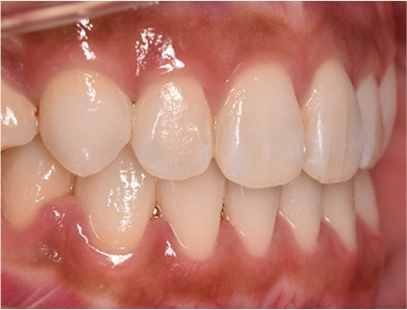

治療後

• 矯正治療後の横顔

• 正面

• 左側

• 右側

治療前の写真と比べると上下の前歯は後方に下がりました。

そのために、鼻の下の膨らみもすっきりして、下唇も薄くなることができました。

治療期間は2年と6か月を必要としました。